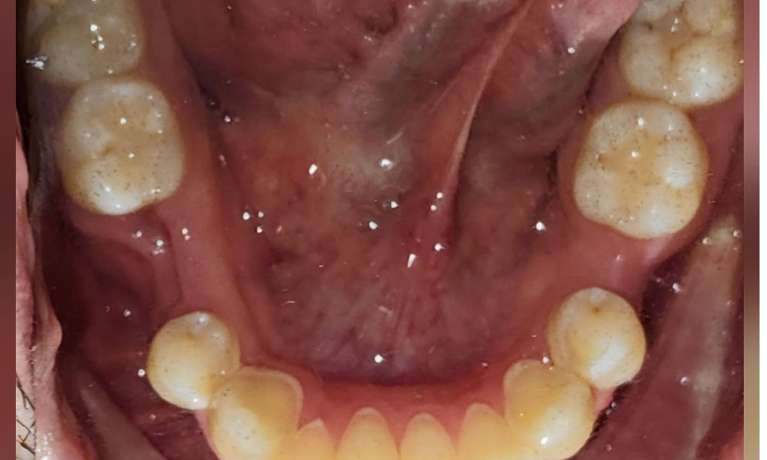

This patient came to us with some front teeth crowding, which was fixed with an Invisalign treatment. This gradually aligned the teeth leading to a straighter and more harmonious smile.